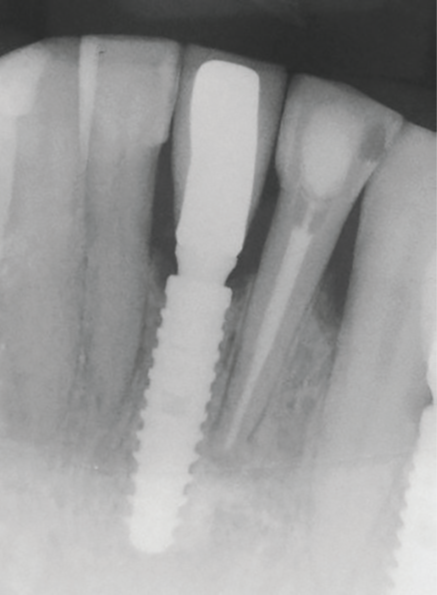

Um paciente com 49 anos de idade buscou atendimentoem clínica privada devido à fratura após um retratamento endodôntico no dente 41 (Figura 1). Mediante a anamnese e análise do exame de tomografia computadorizada de feixe cônico solicitado, foi verificada qualidade óssea do tipo II na área. Então, a decisão clínica baseou-se na cirurgia para exodontia e instalação imediata de um implante dentário.

Após a assepsia com clorexidina 2% e anestesia terminal infiltrativa com mepivacaína 2% com epinefrina 1:100.000, foi selecionado um implante dentário cônico Due Cone (3,5 mm x 13 mm). Foi utilizada a sequência de fresagem com fresa lança helicoidal 2 mm e fresa de 3,5 mm, conforme recomendações do fabricante. O implante foi estabilizado com torque de 45 Ncm. A sutura foi realizada com fio de sutura de seda 4-0, e uma prótese provisória adesiva foi instalada apoiada sobre os dentes vizinhos (sem preparo dentário), permanecendo durante as 12 semanas de espera para o segundo tempo cirúrgico (Figuras 2 e 3).

Na consulta seguinte, a coroa metalocerâmica com liga de níquel-cromo foi instalada no elemento 41 e o orifício de acesso do parafuso foi restaurado com resina composta (Z350, 3M). Uma radiografia periapical foi realizada para posterior controle (Figuras 13 a 15). Após 12 meses, com uma nova avaliação clínica e radiográfica, observou-se a boa manutenção dos tecidos peri-implantares (Figuras 16 e 17).